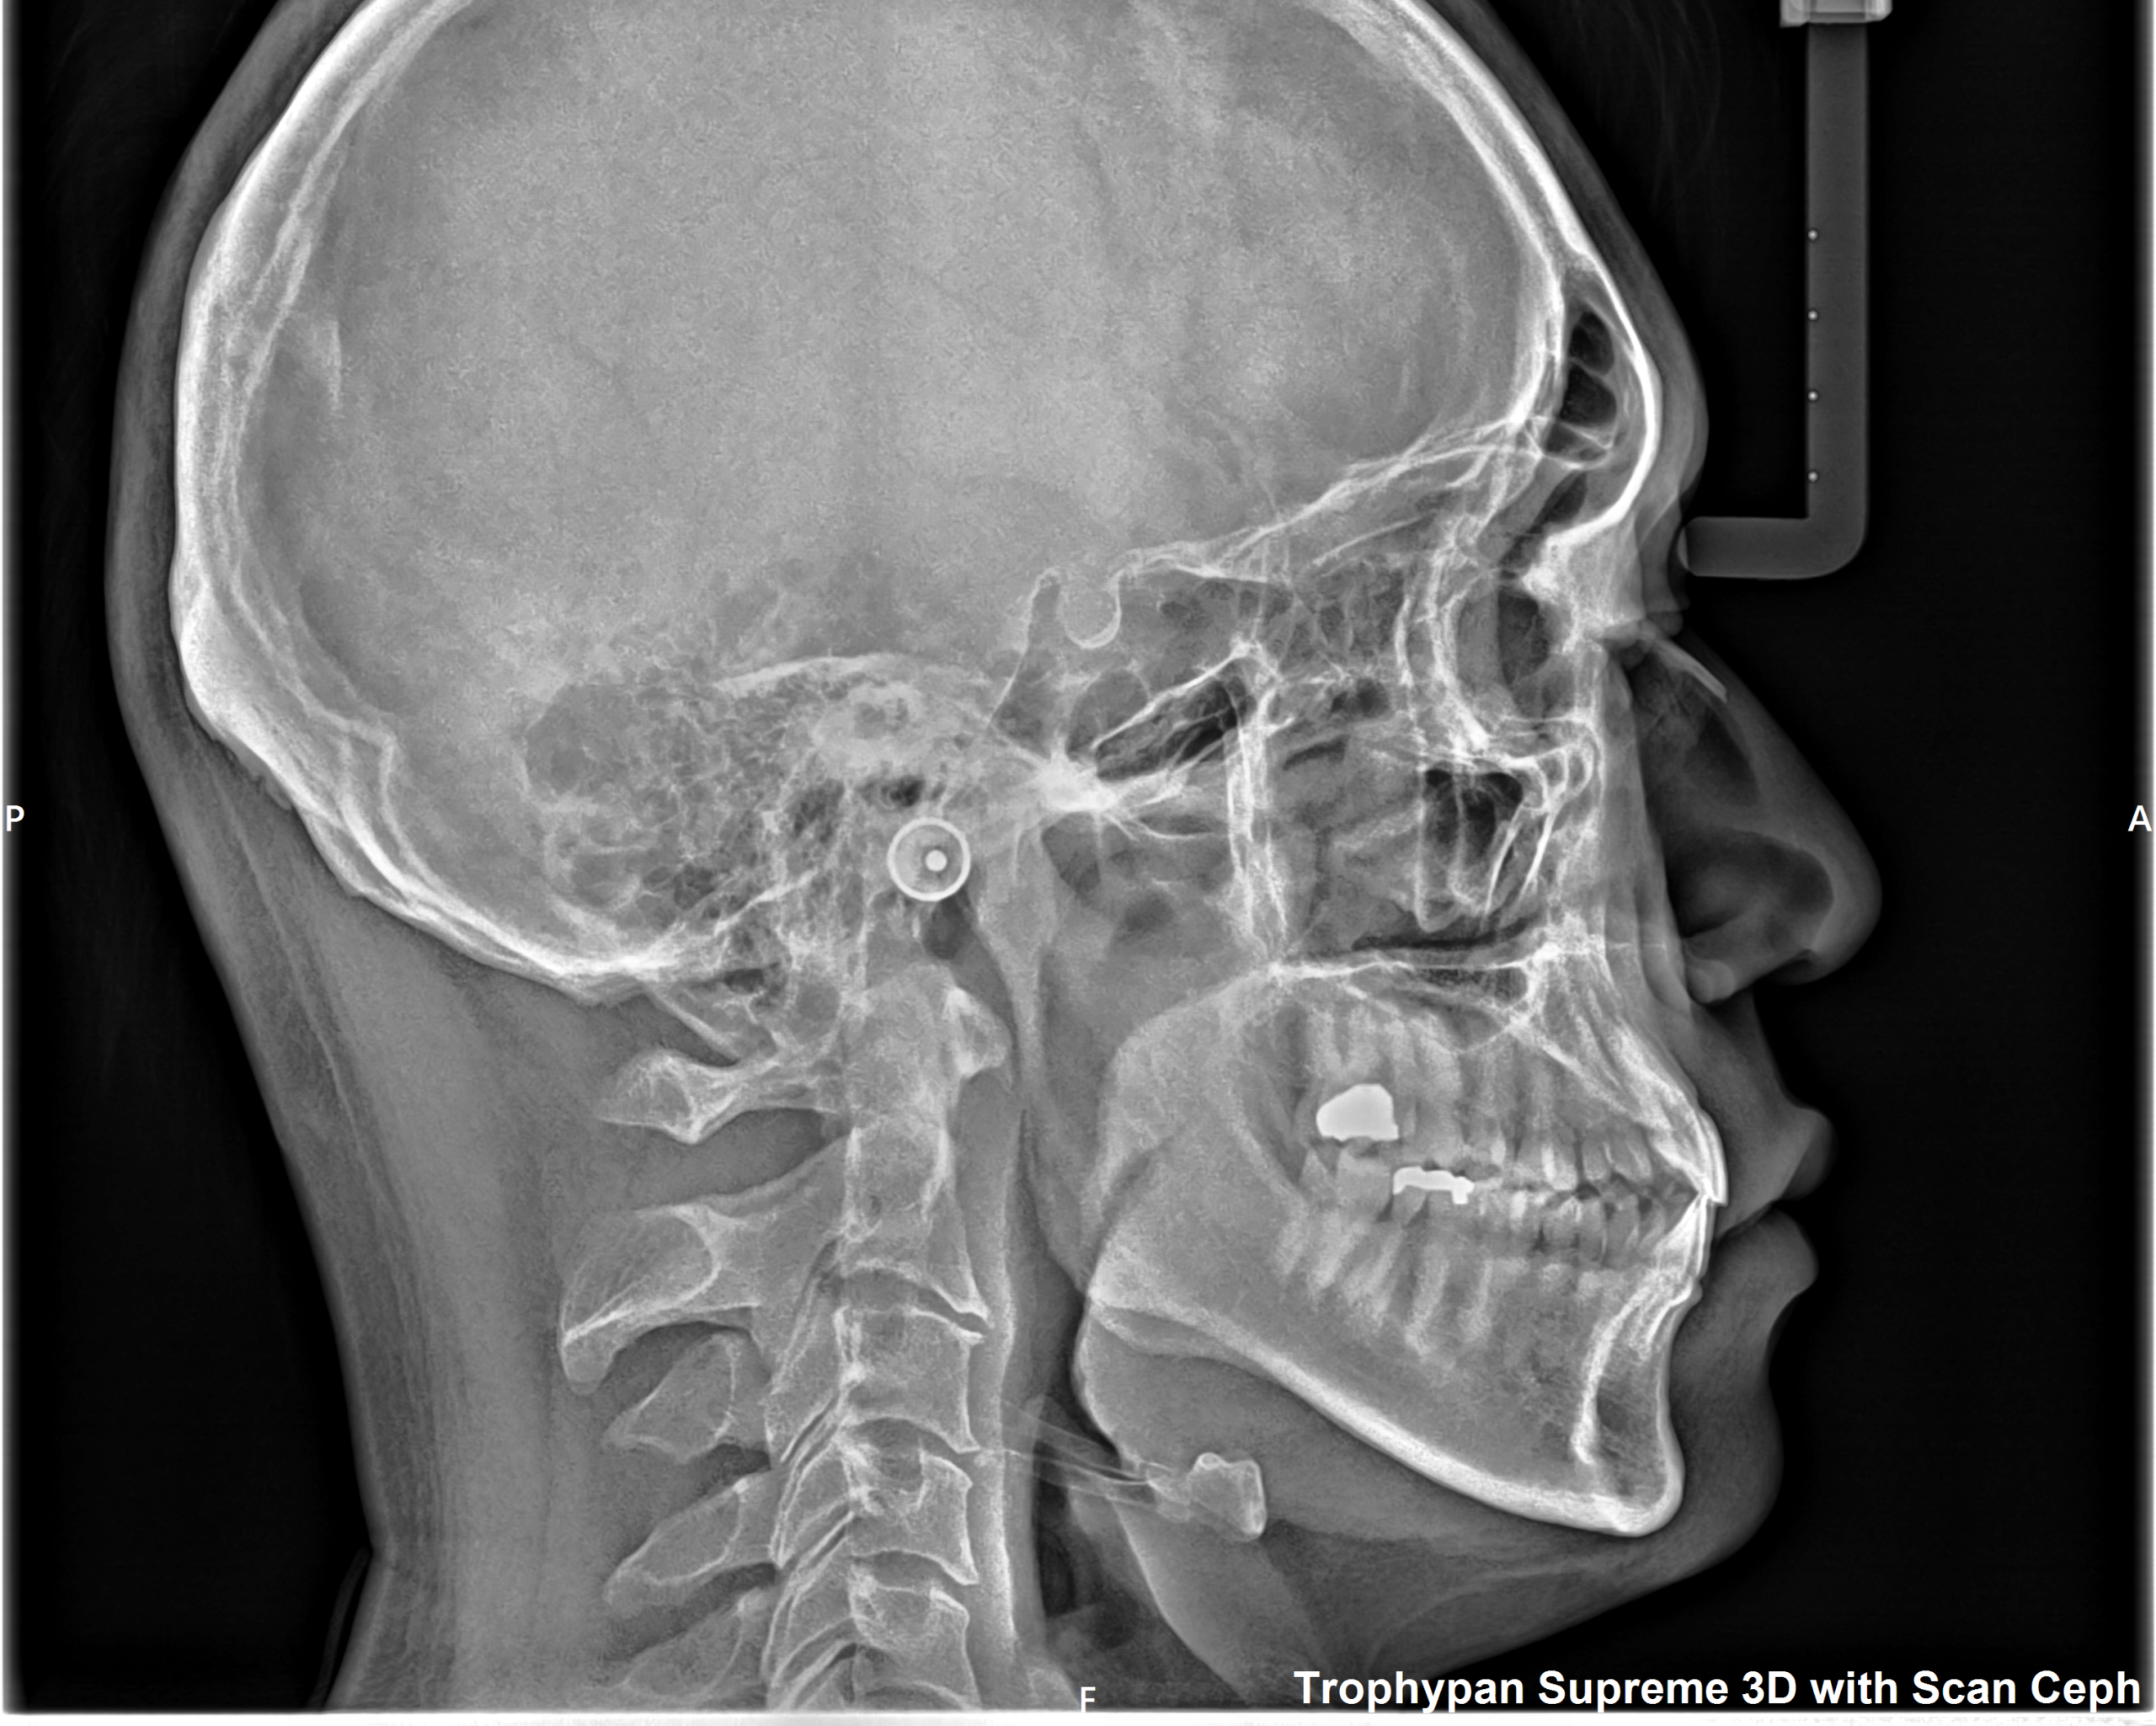

②セファロ写真

側貌写真では、頭部の位置に対する上下顎の前後関係(出っ歯や受け口など)や垂直関係(面長か丸顔かなど)を調べたり、歯の傾きや口元の突出度など様々な要因を数値化して正常値からどれくらい離れているかを確認します。